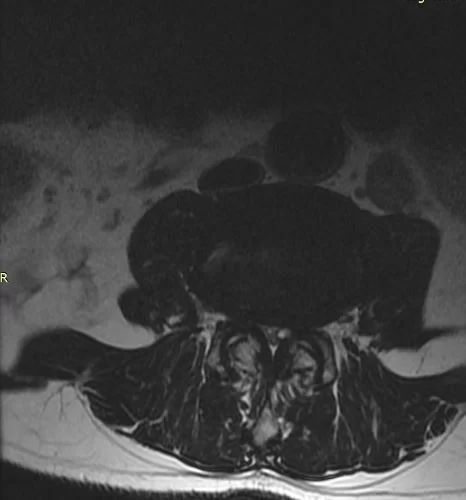

Το τελικό αποτέλεσμα είναι η πλήρης αποσυμπίεση των νεύρων και η άμεση ανακούφιση των συμπτωμάτων του ασθενούς και κυρίως του πόνου ή του αισθήματος βάρους και αδυναμίας στα πόδια κατά τη βάδιση (Εικόνα 4).